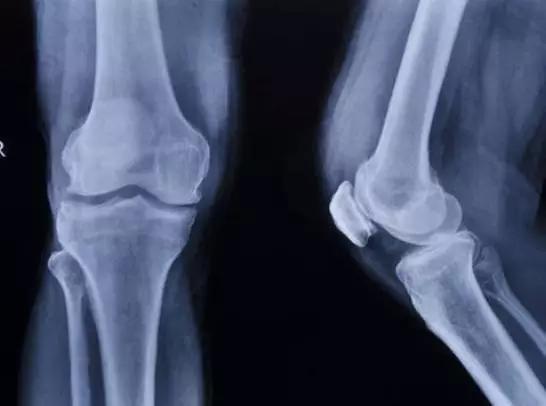

1、24根。人体肋骨12对,左右对称,后端与胸椎相关节,前端仅第1-7肋借软骨与胸骨相连接,称为真肋;第8-12肋称为假肋,其中第8-10肋借肋软骨与上一肋的软骨相连,形成肋弓,第11、12肋前端游离,又称浮肋。

2、第1肋骨短小而弯曲,头和颈稍低于体,肋体扁,可分为上、下两面和内、外两缘。上面内缘处有前斜角肌附着形成的前斜角肌结节,结节的前、后方各有浅沟,是锁骨下静脉和锁骨下动脉的压迹。下面无肋沟,前端借肋软骨直接与胸骨相结合。